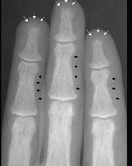

- 单项选择题下列哪项X线表现对甲状旁腺功能亢进症有诊断价值 ( )

D、骨膜下皮质吸收、颅骨斑点状脱钙